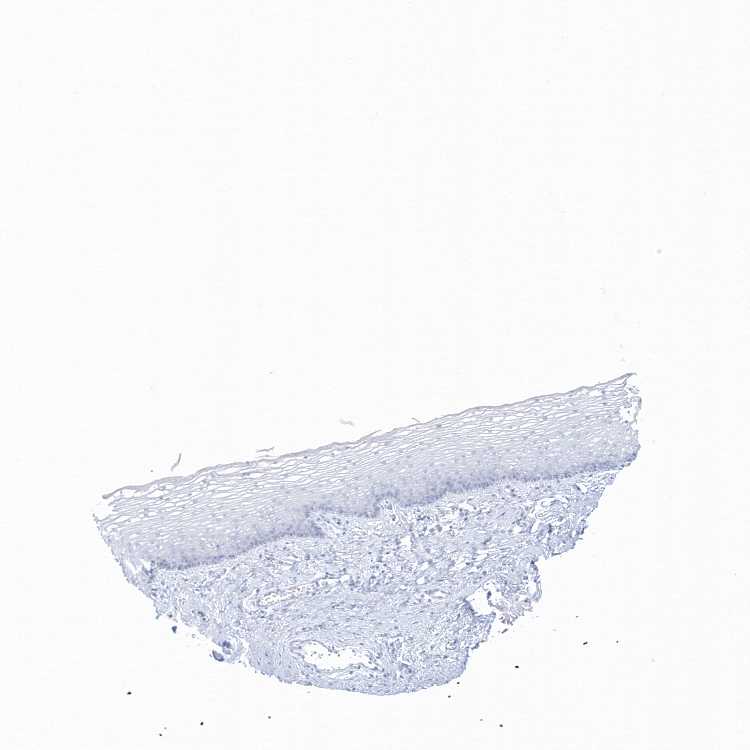

VAGINA - Antibody stainingi

Antibody staining in the annotated cell types in the current human tissue is reported as not detected, low, medium, or high, based on conventional immunohistochemistry profiling in selected tissues. This score is based on the combination of the staining intensity and fraction of stained cells.

Each image is clickable and will lead to virtual microscopy that enables deeper exploration of all samples and also displays staining intensity scores, fraction scores and subcellular localization as well as patient and tissue information for each sample.

Antibody HPA034525

Squamous epithelial cells Not detected